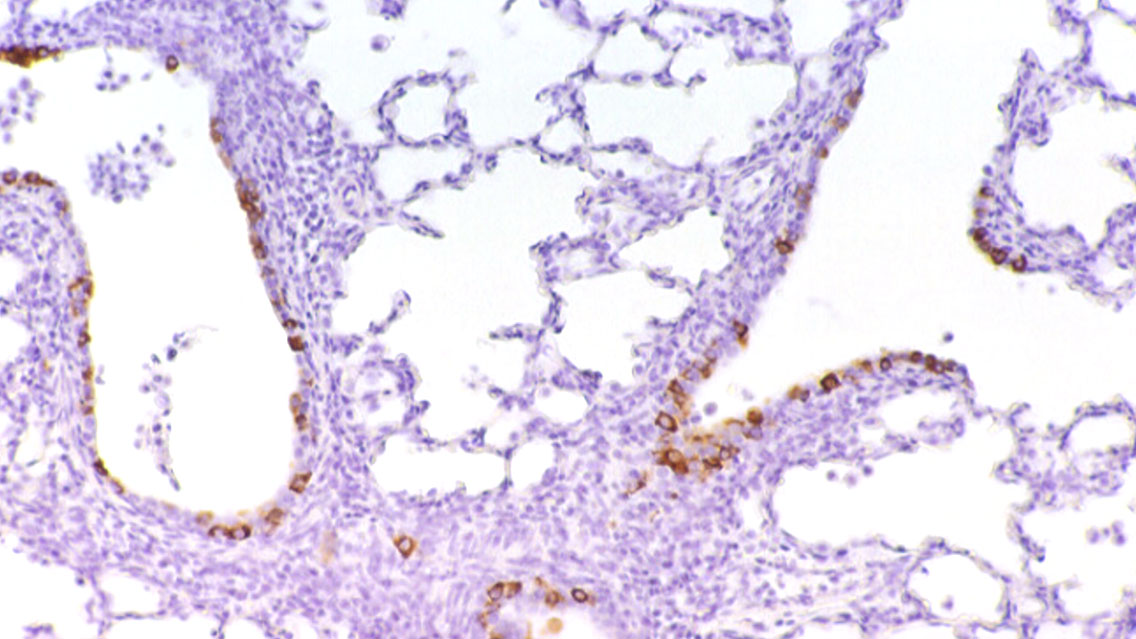

Le lesioni polmonari causate da PCV2 sono macro e microscopiche simili a quelle causate da PRRSV, poiché come questo, provoca polmonite interstiziale, quindi dobbiamo ricorrere ad altre tecniche diagnostiche come l'immunoistochimica (Figura 3), l'ibridazione in situ o la PCR al fine di stabilire la diagnosi. Inoltre, sono due agenti che sono solitamente isolati insieme poiché l'infezione da PRRSV è associata ad un aumento della replicazione e della virulenza del PCV2.